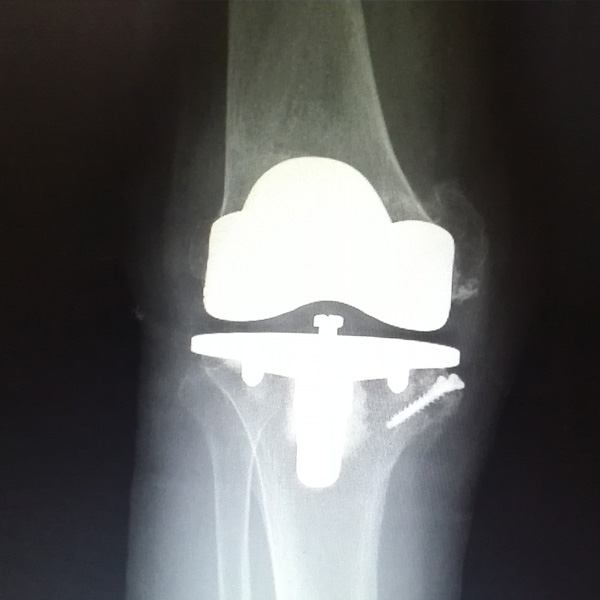

膝關(guān)節(jié)內(nèi)翻

患者劉某某,女66歲,左側(cè)膝關(guān)節(jié)嚴(yán)重內(nèi)翻(俗稱(chēng)的“羅圈腿”),疼痛到不能生活自理。經(jīng)平臺(tái)推薦到哈爾濱醫(yī)科大學(xué)附屬第二醫(yī)院骨關(guān)節(jié)科就診,......